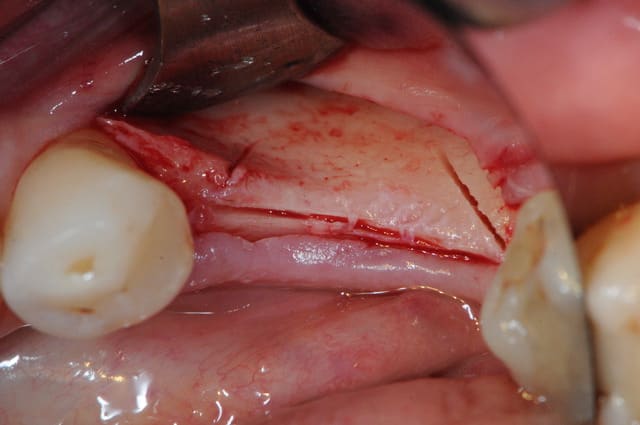

Cas 1-coté gauche maintenant:

1- ouverture, forme et configuration différente

2- une fois échauffée avec le coté droit, je me dis allez hop, j'attaque une expansion. donc incision crestale avec décharges osseuses

3- mise en place des expanseurs de Mesinger A et B

4-5 notez que l'incision de décharge étant oblique , elle sert également de garde fou contre une éventuelle fracture osseuse. l'os "mobile" vient buter contre l'os "immobile"

Bravo D57 pour ta chirurgie de reconstruction avec le systeme Fast.

mais j'ai quelques remarques:

1. tes vis ne sont pas positionnées comme il faut.

2. tes vis sont trop enfouies

3. tes sutures ne sont pas assez profondes. comme je te le disais à l'ADF, tu dois être à au moins 1 cm de la berge.

4. Donc, je peux te le dire d'avance: le résultat sera moyen. Je t'avais proposé de préparer ensemble le protocole chirrugical. dommmage.